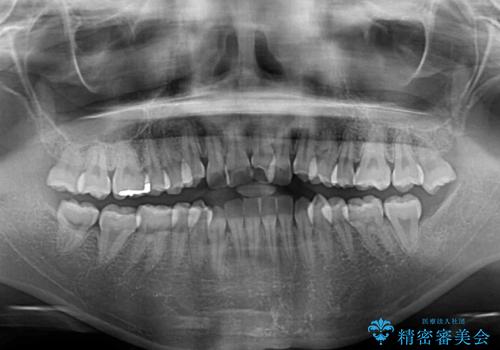

- 前歯のデコボコとクロスバイトを治したいとのことで来院された患者様です。

上下顎ともに歯列全体の側方拡大とIPR(歯と歯の間を削る)によってデコボコとクロスバイトが解消するように設計し、インビザラインにより治療を行うこととしました。

下顎骨の左側への骨格的なずれが強く、上下の正中の位置合わせや奥歯の咬み合わせ構築に苦労しました。